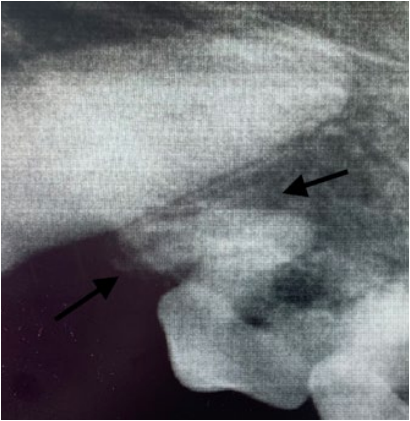

В случаях, когда постоянный зуб прорезывается неестественным путем или его зачаток располагается таким образом, что не может запустить процесс разрушения временного зуба, он прорезывается рядом. В результате смены зуба не происходит (за исключением процесса боковой резорбции, возникающей не на верхушке корня зуба, а на боковой поверхности временного корня, когда зубы находятся в плотном боковом контакте) (фото 1).

- Неправильная траектория прорезывания (фото 2). Такая патология может возникать из-за нарушения развития альвеолярного отростка в результате какого-либо механического препятствия, нарушения закладки зачатков зубов в раннем эмбриональном периоде, а также по причине дефицита места.